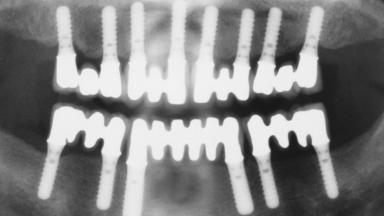

Immediate Loading of Eight Implants in the Maxilla and Six Implants in the Mandible and Final Restoration with Three-Unit and Four-Unit FDPs

Extensive scientific evidence has confirmed that immediately loaded implants with fixed full-arch provisional restorations can osseointegrate with success rates similar to conventionally or delayed loaded implants. A number of immediate-provisionalization techniques for edentulous jaws have been described. Some protocols differ when it comes to prefabricated provisional templates versus complete denture conversion; intrasurgical impressions versus direct relining; and cemented versus screw-retained provisional restorations. In this context, complete-denture conversion has been proposed for either intrasurgical impressions or direct relining. Another possibility is the utilization of a prefabricated provisional to be adapted either in the mouth (by direct relining) or in the laboratory (on a working model obtained from an intrasurgical impression).